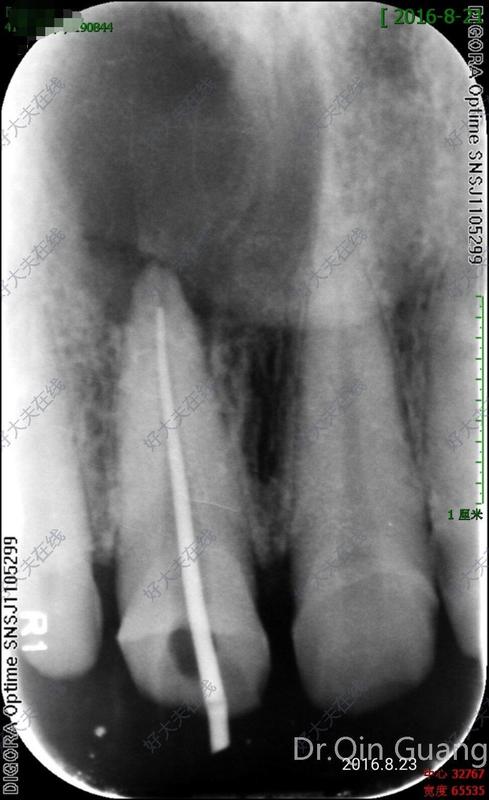

外院因根尖大面積陰影轉(zhuǎn)診廣州光華口腔要求根管治療后行根尖手術(shù);該患牙有個(gè)特點(diǎn)反復(fù)封藥很多次,根管內(nèi)即使用大量次氯酸鈉沖洗,還是始終充滿囊液,根管叩診一直輕度不舒服,最后選擇改良式根管治療,患者3年后隨訪一切正常!診療體會(huì):目前國(guó)內(nèi)大量這樣的病例很多采用根尖手術(shù)治療,但很多僅僅需要根管治療就可以治好,所以根尖手術(shù)的適應(yīng)癥還需深入討論,減少患者不必要的費(fèi)用付出和創(chuàng)傷。